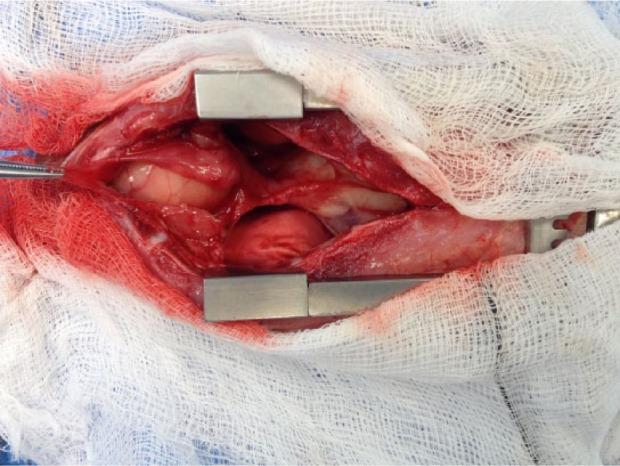

An 18-month-old female domestic shorthair cat was referred for investigation of a 6 month period of regurgitation. Contrast radiography indicated an intramural oesophageal structure. Ultrasound-guided fine-needle aspiration of the area retrieved viscous fluid containing high numbers of squamous epithelial cells. Computed tomography disclosed a thin-walled contrast-enhancing structure containing non-enhancing homogenous contents. Exploratory thoracotomy confirmed an intramural cystic oesophageal structure, which was resected. Histopathological analysis of the resected tissue demonstrated an intramural oesophageal duplication cyst. A 12 month follow-up period has seen complete resolution of the cat's clinical signs.

一只18个月大的雌性家猫因6个月的反流症状被转诊进行检查。造影显示食管壁内有一个结构。超声引导下对该区域进行细针穿刺抽吸,获取了含有大量鳞状上皮细胞的粘性液体。计算机断层扫描显示一个薄壁的、有造影剂增强的结构,其内容物无造影剂增强且均匀一致。开胸探查证实为食管壁内的囊性结构,并将其切除。对切除组织进行组织病理学分析显示为食管壁内重复囊肿。经过12个月的随访,这只猫的临床症状完全消失。